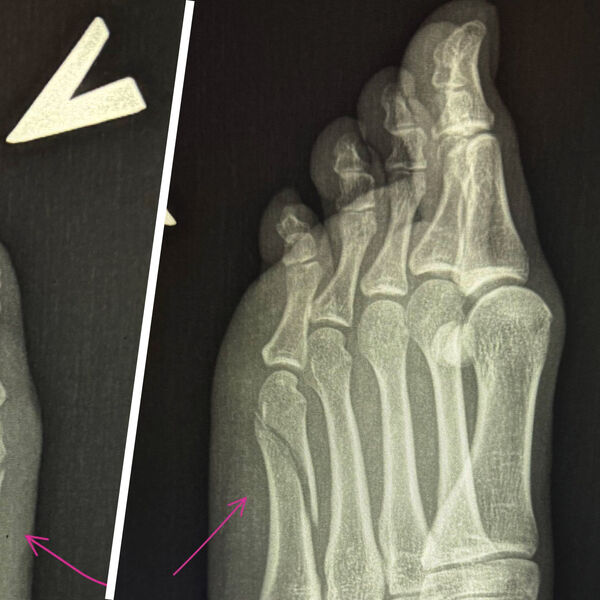

Вавилова опубликовала сообщение в ночь на 28 сентября 2025 года, приложив к нему рентгеновские снимки, на которых видна трещина в кости, ведущей к мизинцу. Она отметила, что из-за травмы не может заниматься привычными делами и вынуждена оставаться дома для отдыха.